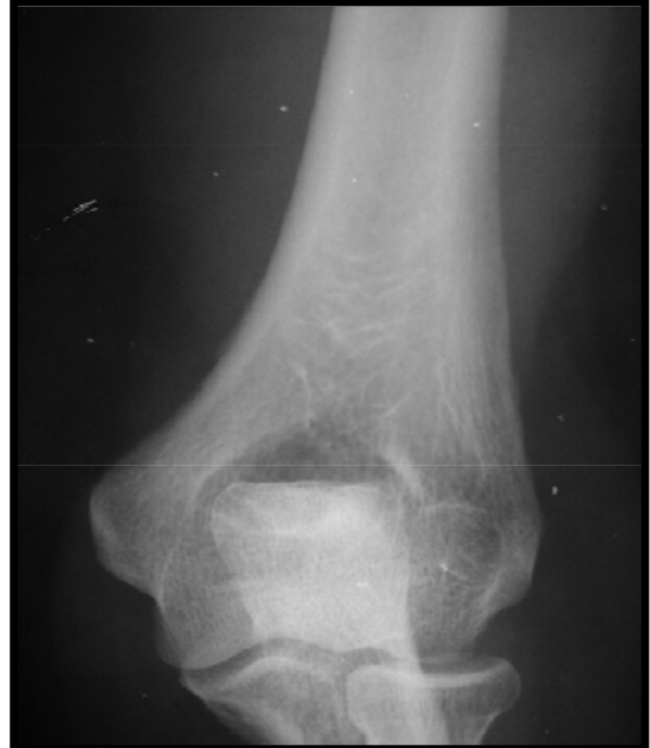

Nutrient vessel entrance

variation anat normal